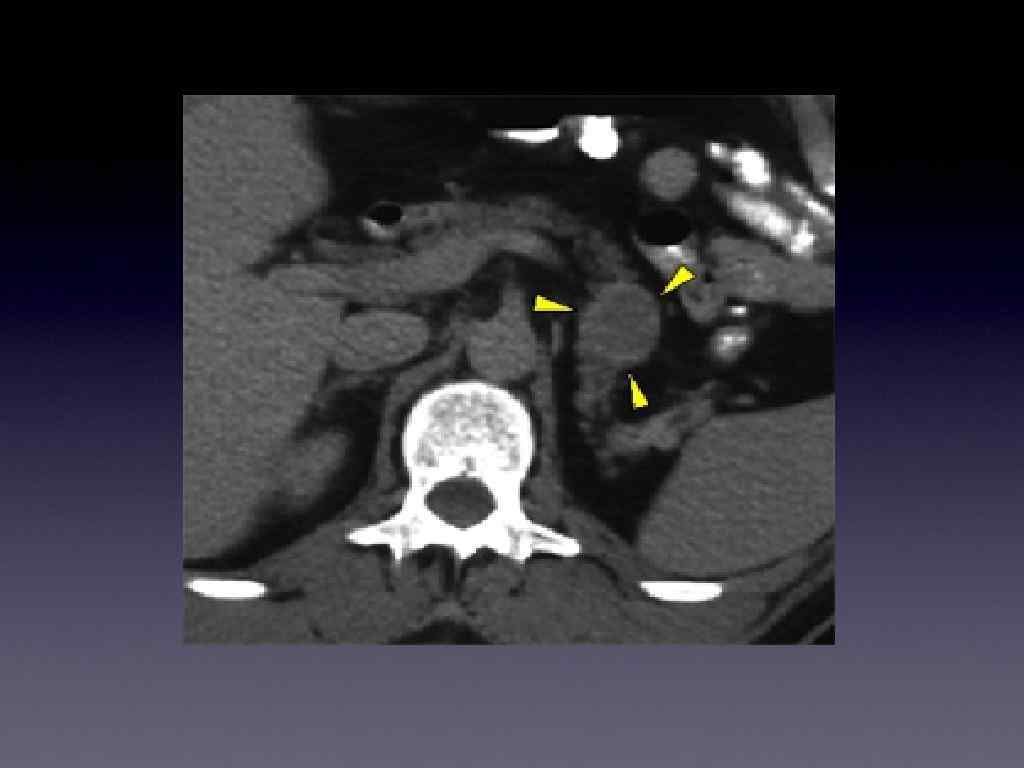

Топическая диагностика инсулиномы • Ангиографическая диагностика • Кт • МРТ • УЗИ • Катетерезация портальной вены с целью определения уровня ИРИ